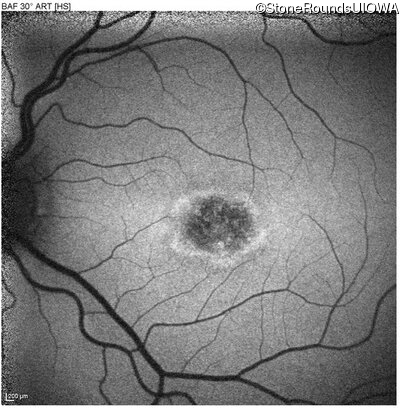

Blue Autofluorescence - Left - 20/125 -2 sc

Exemplar